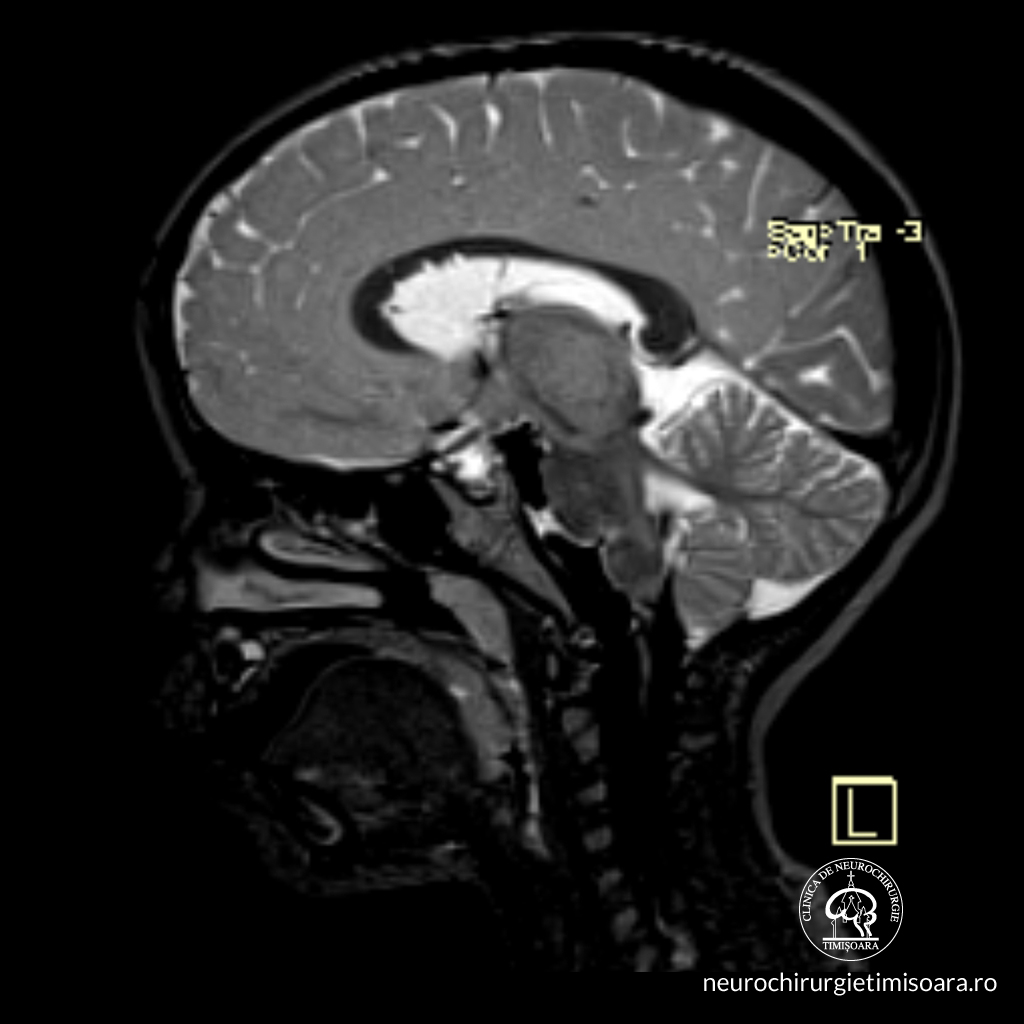

Neurochirurgie pediatrica